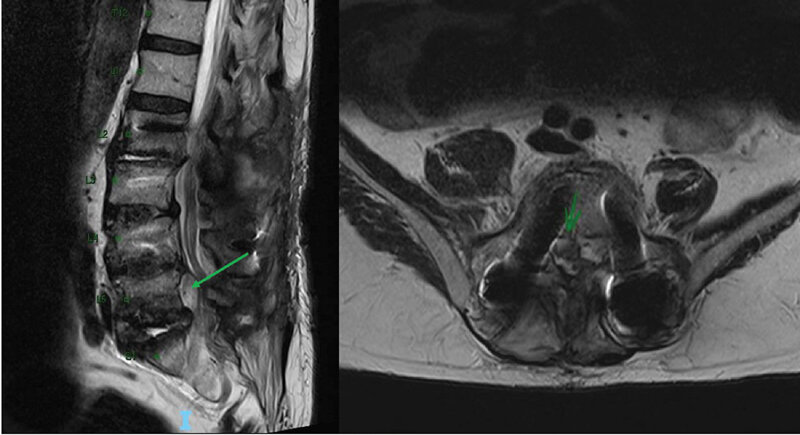

Na ressonância magnética, as sequências T2 e T2* têm objetivos diferentes. O T2 tradicional (Spin Echo ou FSE) destaca estruturas com alto teor de água, como o líquido cefalorraquidiano, edema e inflamações. Já o T2* (Gradient Echo ou SWI) é extremamente sensível a variações de campo magnético, como sangue, calcificações e metais.

- Uso comum: Edema cerebral, abcessos, tumores, lesões medulares.